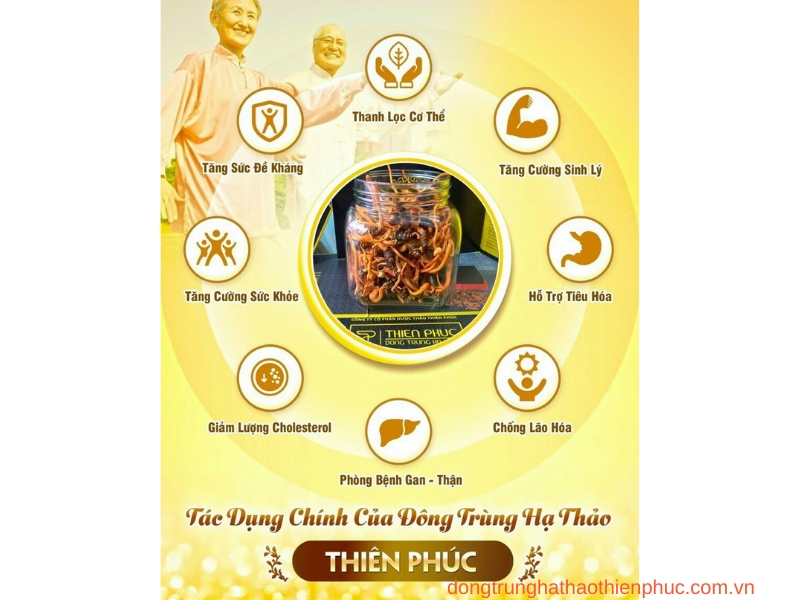

Cordyceps Sinensis, còn gọi là đông trùng hạ thảo, từ lâu đã được xem như một dược liệu quý trong y học cổ truyền nhờ vào khả năng tăng cường sức khỏe toàn diện. Loại thảo dược này chứa nhiều thành phần quý giá, bao gồm các axit amin, vitamin và khoáng chất, giúp cải thiện hệ miễn dịch, hỗ trợ chức năng gan, phổi, và tăng cường sinh lý. Dưới đây là những tác dụng nổi bật của Cordyceps Sinensis đối với sức khỏe con người.

1. Tăng Cường Hệ Miễn Dịch

Cordyceps Sinensis có khả năng hỗ trợ hệ miễn dịch, giúp cơ thể chống lại các vi khuẩn và virus gây bệnh. Loại thảo dược này kích thích sự sản xuất và hoạt động của các tế bào miễn dịch, giúp bảo vệ cơ thể trước các tác nhân gây hại từ môi trường.

- Công dụng của Cordyceps Sinensis với hệ miễn dịch: Các nghiên cứu cho thấy Cordyceps Sinensis giúp tăng cường miễn dịch tự nhiên, hỗ trợ cơ thể chống lại các bệnh nhiễm trùng, cảm cúm và các bệnh thường gặp khác.

- Tăng cường sức đề kháng: Loại thảo dược này đặc biệt có lợi cho những người có hệ miễn dịch suy giảm, bao gồm người già và những người bị căng thẳng kéo dài.

3. Tăng Cường Sinh Lý Và Sức Khỏe Sinh Sản

Một trong những lợi ích của Cordyceps Sinensis với sinh lý là khả năng tăng cường sinh lực và hỗ trợ sức khỏe sinh sản. Đối với nam giới, Cordyceps Sinensis giúp cải thiện chức năng thận, tăng cường sức mạnh và khả năng tình dục tự nhiên. Điều này là nhờ vào tác dụng kích thích tuần hoàn máu và sản xuất hormone sinh dục.

- Cordyceps Sinensis tăng cường sinh lý: Cordyceps Sinensis giúp nam giới cải thiện sinh lực, giảm thiểu tình trạng mệt mỏi và tăng cường năng lượng.

- Hỗ trợ sinh sản: Loại thảo dược này còn có thể cải thiện chất lượng tinh trùng, giúp nâng cao khả năng sinh sản.

5. Hỗ Trợ Chức Năng Gan Và Thận

Cordyceps Sinensis có tác dụng tuyệt vời trong việc giải độc gan và bảo vệ chức năng thận. Các thành phần trong loại thảo dược này giúp gan lọc độc tố hiệu quả và giảm các tổn thương từ các chất độc hại, đồng thời hỗ trợ chức năng lọc máu của thận.

- Công dụng Cordyceps Sinensis với chức năng gan: Đối với người thường xuyên sử dụng thuốc đặc trị hoặc có thói quen uống rượu bia, Cordyceps Sinensis giúp gan thải độc và cải thiện chức năng lọc của gan.

- Tác dụng với thận: Loại thảo dược này còn giúp bảo vệ thận trước các nguy cơ suy giảm chức năng do tuổi tác hoặc bệnh lý mãn tính.

6. Chống Lão Hóa Và Tăng Cường Năng Lượng

Cordyceps Sinensis là một chất chống oxy hóa tự nhiên mạnh mẽ, giúp ngăn ngừa lão hóa và giữ cơ thể luôn trong trạng thái khỏe mạnh. Loại thảo dược này giúp tái tạo tế bào, giữ gìn sức khỏe và cải thiện tinh thần, từ đó giúp người dùng luôn năng động và dồi dào năng lượng.

- Cordyceps Sinensis chống lão hóa: Các chất chống oxy hóa trong Cordyceps giúp làm chậm quá trình lão hóa tế bào, duy trì sức khỏe và tăng cường tuổi thọ.

- Cải thiện năng lượng cơ thể: Sử dụng Cordyceps Sinensis giúp cơ thể duy trì năng lượng và sức khỏe bền vững, đặc biệt là ở người cao tuổi.

Kết Luận

Cordyceps Sinensis là dược liệu quý với nhiều công dụng đối với sức khỏe con người. Từ việc tăng cường hệ miễn dịch, hỗ trợ chức năng tim mạch, gan thận, cho đến chống lão hóa, Cordyceps Sinensis là giải pháp hoàn hảo cho những ai mong muốn chăm sóc sức khỏe toàn diện và tự nhiên. Hãy cân nhắc bổ sung loại thảo dược này vào chế độ ăn uống hàng ngày để đạt được lợi ích tối đa cho sức khỏe của bạn.